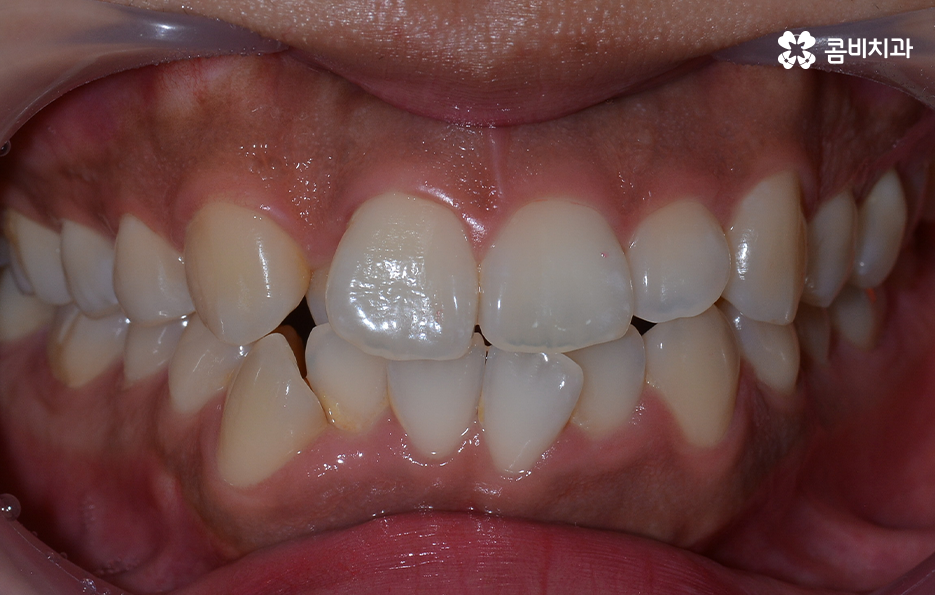

앞니의 덧니가 심하고 겹쳐 있는 경우에는 교합이 제대로 맞물리지 않거나 이물질이 치아 사이에 끼기 쉽고 그로 인해 치석이 쌓이기 때문에 나이가 들수록 덧니를 방치할 경우 충치 뿐 아니라 치주질환의 가능성이 높아지고 있는데요

덧니 교정을 통해서 치아 교합의 기능적 개선과 치아 관리의 용이성 높일 수 있고 치아 건강에도 도움이 되며 심미적인 개선도 도움이 될 수 있어요

심한 덧니로 고민하시는 분들은 환하게 웃고 싶지만 입을 가리고 웃는다거나 돌출입으로 인해 가만히 있어도 입이 벌어지는 등의 불편함을 느끼시는 분들이 많기 때문에 치아교정을 통한 치열의 개선 뿐 아니라 자신감의 향상, 얼굴 외형적인 변화까지 얻을 수 있기 때문에 그만큼 정확한 검진과 치료 예측을 통해 치아교정 계획을 잘 세우는 것이 그만큼 중요할 거예요